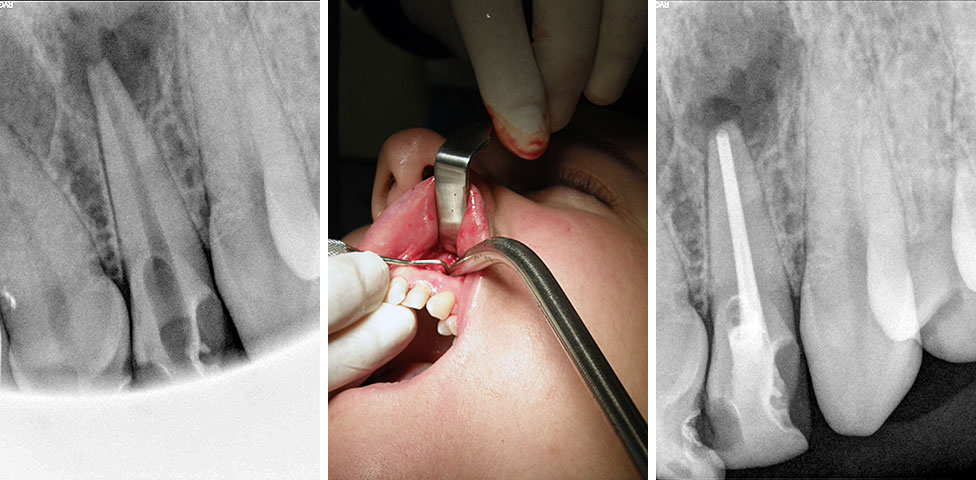

Endodoncija